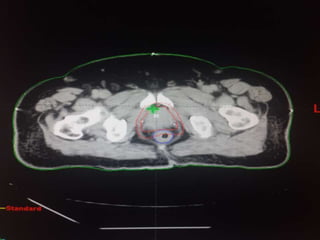

Our unit decide to treat:

 Prostate + S.V & prophylactic Pelvic LNs in

phase1

 Prostate + S.V phase 2

 Delineation of our unit illustrated in the

following slides:

Our unit decideto treat:  Prostate + S.V & prophylactic Pelvic LNs in phase1  Prostate + S.V phase 2  Delineation of our unit illustrated in the following slides: